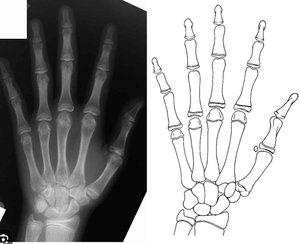

Relationship between hand and wrist bone age assessment methods - PMC

Figure 2 from Classification of hand-wrist maturity level based on ...

Digital radiographic evaluation of hand-wrist bone maturation and ...